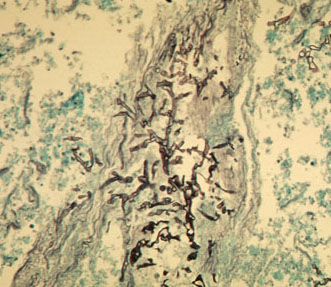

- Aspergillosis: septate, true hypae with acute angle branding

- Mucormycosis: non-septate, true hyphae, broad, ribbon-like, with

wide angle branching

GMS